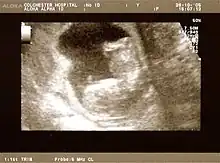

Fetal assessments

Obstetric ultrasonography is routinely used for dating the gestational age of a pregnancy from the size of the fetus, determine the number of fetuses and placentae, evaluate for an ectopic pregnancy and first trimester bleeding, the most accurate dating being in first trimester before the growth of the foetus has been significantly influenced by other factors.[22] Ultrasound is also used for detecting congenital anomalies (or other foetal anomalies) and determining the biophysical profiles (BPP), which are generally easier to detect in the second trimester when the foetal structures are larger and more developed.[23]

X-rays and computerized tomography (CT) are not used, especially in the first trimester, due to the ionizing radiation, which has teratogenic effects on the foetus.[24] No effects of magnetic resonance imaging (MRI) on the foetus have been demonstrated,[25] but this technique is too expensive for routine observation. Instead, obstetric ultrasonography is the imaging method of choice in the first trimester and throughout the pregnancy, because it emits no radiation, is portable, and allows for realtime imaging.[26]

The safety of frequent ultrasound scanning has not been confirmed. Despite this, increasing numbers of women are choosing to have additional scans for no medical purpose, such as gender scans, 3D and 4D scans.[27] A normal gestation would reveal a gestational sac, yolk sac, and fetal pole.[28]

The gestational age can be assessed by evaluating the mean gestational sac diameter (MGD) before week 6, and the crown-rump length after week 6. Multiple gestation is evaluated by the number of placentae and amniotic sacs present.[29]